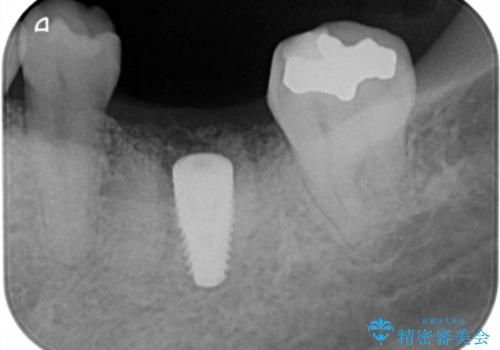

失った奥歯をインプラントで機能回復

- 44万円(インプラント・チタンカスタムアバットメント・ジルコニアクラウン・仮歯)費用は治療当時の料金となります

元あった歯のようにしっかりと咬合機能が回復することができました。